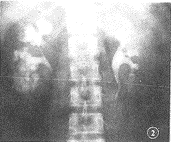

例1:女,41岁,诉右腰背痛1周,伴有尿频、尿急3 d门诊就医。体检:右肾区叩击痛(++),尿检:镜下红细胞少许。B超检查:右肾结石。临床拟诊右肾结石。X线所见:平片右肾区见有无数小砂粒状结石影,呈条纹状,斑点丛状聚合(图1)。静脉尿路造影:右肾髓质区呈条纹状、囊状密度增高,结石位于扩张的集合小管内,小盏杯口与扩张的集合小管重叠(图2)。解压后,扩张集合小管排空延迟、肾盂输尿管管壁柔软,膀胱显影良好。左侧无异变。诊断:右侧髓质海绵肾。

图2 右肾髓质区呈花朵状、葡萄串样密度增高、无数小结石重叠于造影剂中